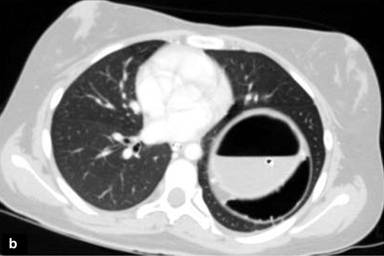

Laboratory investigations showed the patient to be anaemic (Hb 9 gm%) with leucocytosis (16,000/cubic mm) and a predominance of polymorphonuclear cells (80%). Scanogram revealed a dilated stomach with inverse orientation as evidenced by the position of the Ryle’s tube (Figure 1). A screening abdominal ultrasound failed to demonstrate the spleen in the left hypochondrium. The spleen was present in the umbilical region and extended into the left lumbar region. The bowel loops occupied the left upper quadrant. A contrast enhanced computed tomography (CECT scan) of the chest and abdomen was performed. It depicted a grossly distended stomach with the fundus lying in the left hemi-thorax and an air-fluid level within (Figure 2). The pylorus lay close but a little above the gastro-oesophageal junction, a finding consistent with gastric volvulus (Figure 3). There were no accompanying signs of gastric infarction. An enlarged spleen was visualised occupying the umbilical and the left lumbar region, extending along the undersurface of the left lobe of the liver and reaching below the lower pole of the left kidney (Figures 4, 5). The splenic pedicle had undergone torsion with consequent volvulus of pancreatic tissue. The splenic parenchyma however, had a homogenous attenuation, thus excluding any splenic ischemia. The pancreas was seen compressed between the stomach and the spleen (Figures 3, 5). A diagnosis of pancreatic volvulus due to torsion of wandering spleen, diaphragmatic hernia with an intra-thoracic gastric volvulus and resultant gastric outlet obstruction was thus established.

Figure 3. Axial CT scan abdomen shows the gastro-esophageal junction with Ryle’s tube in situ (blue arrow) and the pylorus (red arrow) with compression of the pancreatic tissue (yellow arrow). |